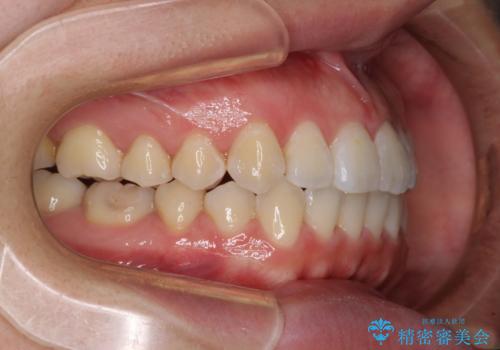

前歯のデコボコを治したい ワイヤー矯正

- 前歯のデコボコが気になるとのことで来院された患者様です。

目立たない装置と金属のワイヤーで矯正治療を行うこととしました。

1年半程度の期間を見込んでいましたが、上下の真ん中の位置をできる限り合わせるための調整に少し時間がかかってしまいました。

咬み合わせが安定し、前歯の汚れも付きにくくなりました。